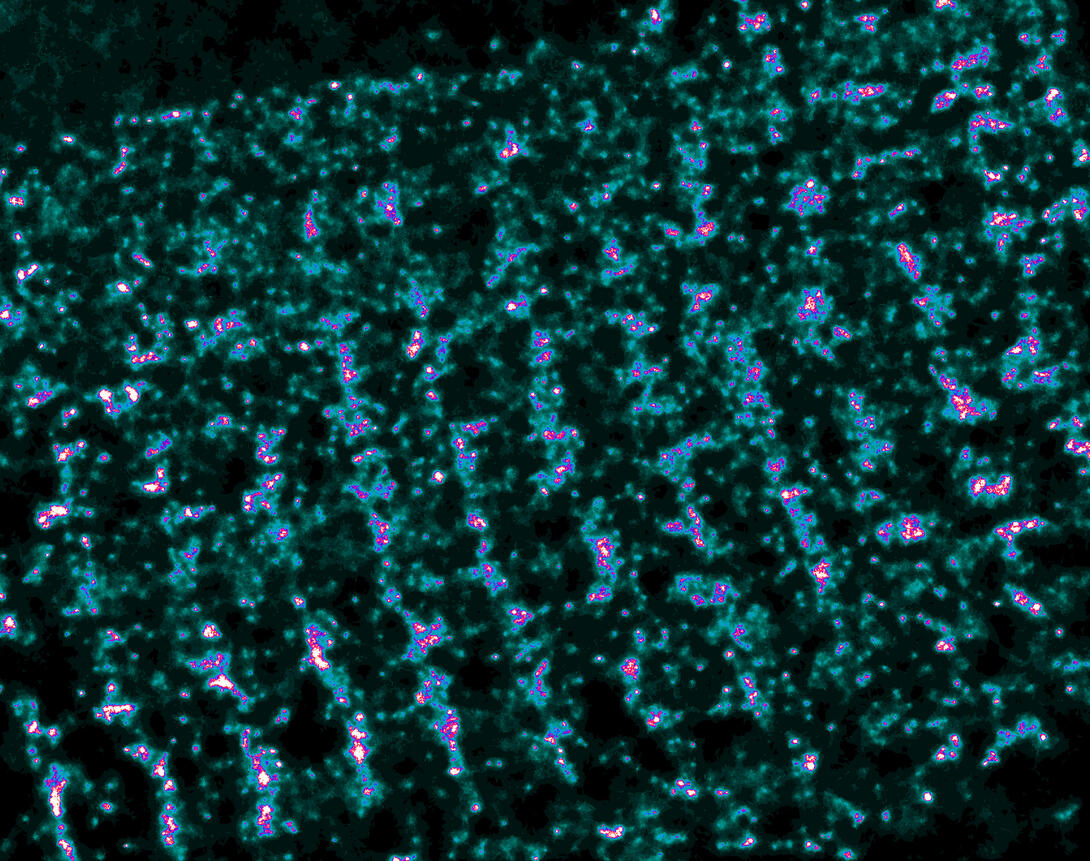

This is a super-resolution light microscope image taken by Hiro Hakozaki and Masa Hoshijima of NCMIR. The image contains highlighted calcium channels in cardiac muscle using a technique called dSTORM. The microscope used in the NCMIR lab was built by Hiro Hakozaki.